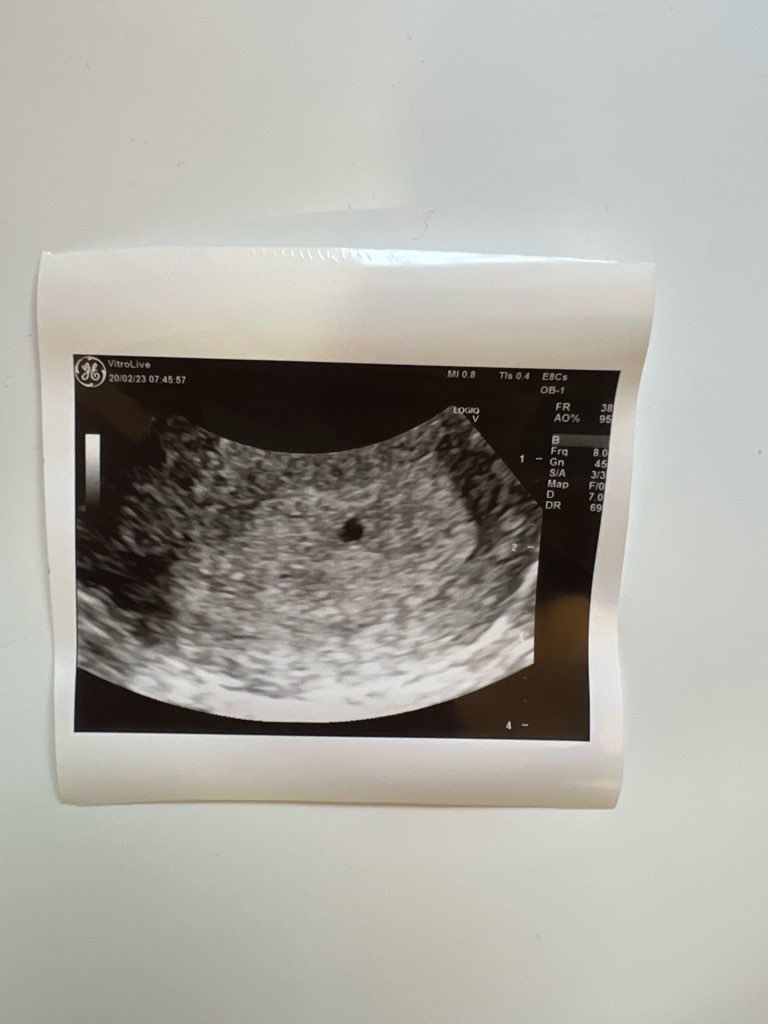

Dziewczyny, ja tez już po wizycie, u mnie dziś 5+3, narazie sam pęcherzyk widać, za tydzień we worek kolejna wizyta. Dostałam dupka ze względu na policystyczne jajniki i czekamy. Trzymam za nas wszystkie kciuki!!

Załączniki

• IMG_5490.jpeg

IMG_5490.jpeg

62,8 KB · Wyświetleń: 88